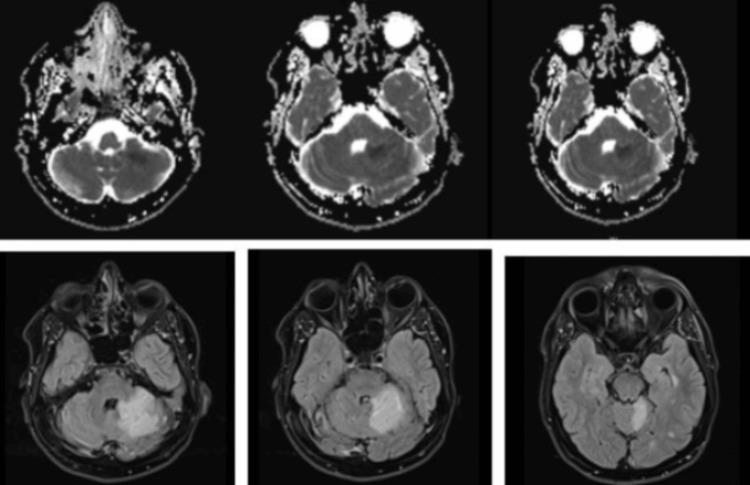

The case describes a middle-aged man with well-managed multiple sclerosis who experienced an acute ischemic stroke attributed to a rare anatomical variant - a duplicated left superior cerebellar artery (SCA). Despite his prior lack of neurological issues, the patient presented with severe headaches and walking difficulties. Imaging confirmed the ischemic stroke in the left SCA territory and revealed the duplicated left SCA. This case highlights the importance of considering cerebrovascular anatomy in stroke risk assessment, especially in individuals with unique vascular features such as duplicated SCAs, which can predispose to vascular complications.

该病例描述了一名患有多发性硬化症且病情得到良好控制的中年男性,他经历了一次急性缺血性中风,病因是一种罕见的解剖变异——左侧小脑上动脉(SCA)重复。尽管患者此前没有神经系统问题,但此次出现了严重头痛和行走困难。影像学检查证实左侧SCA区域发生了缺血性中风,并发现了左侧SCA重复。该病例强调了在中风风险评估中考虑脑血管解剖结构的重要性,尤其是在具有独特血管特征(如SCA重复)的个体中,这种特征可能易引发血管并发症。